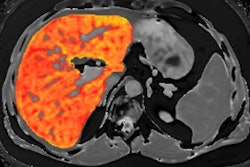

In other Perspectum news, the company is directing attention to a new research study that reported positive results for its LiverMultiScan software. The study, published April 10 in PLOS One, demonstrated the technical performance of LiverMultiScan for measuring three key liver disease biomarkers: iron, fibro-inflammation, and fat, according to the firm.

The researchers from Perspectum, the University of Oxford in the U.K., and the University of Westminster in London found that multiparametric MRI was a repeatable and reproducible method for quantifying liver tissue characteristics, even across equipment from different vendors and field strengths.